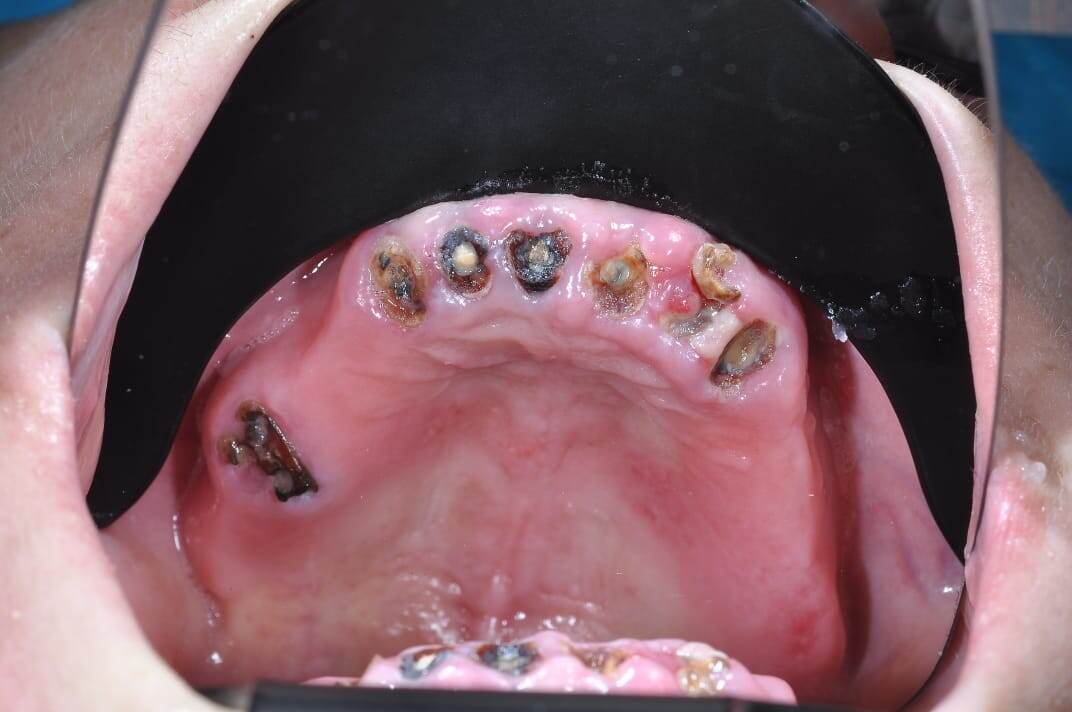

Зубы на фотографии не подлежат лечению в связи с деменерализацией твердых тканей.

Или приходиться удалять все зубы 🦷.